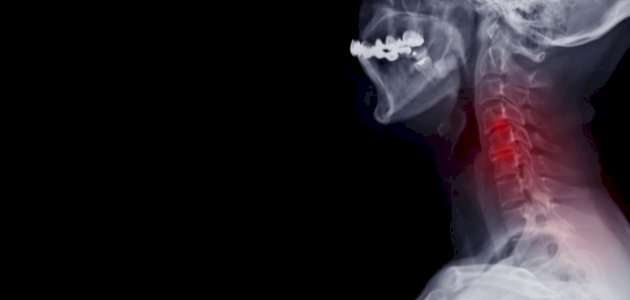

علاج الانزلاق الغضروفي في الرقبة

عمون - يُعاني البعض من الانزلاق الغضروفي في الرقبة (Cervical Herniated Disc)، ويمكن اتخاذ بعض التدابير المنزلية لتخفيف الألم المصاحب لهذه الحالة. فيما يلي توضيح لبعض الإجراءات التي يمكن اتخاذها: